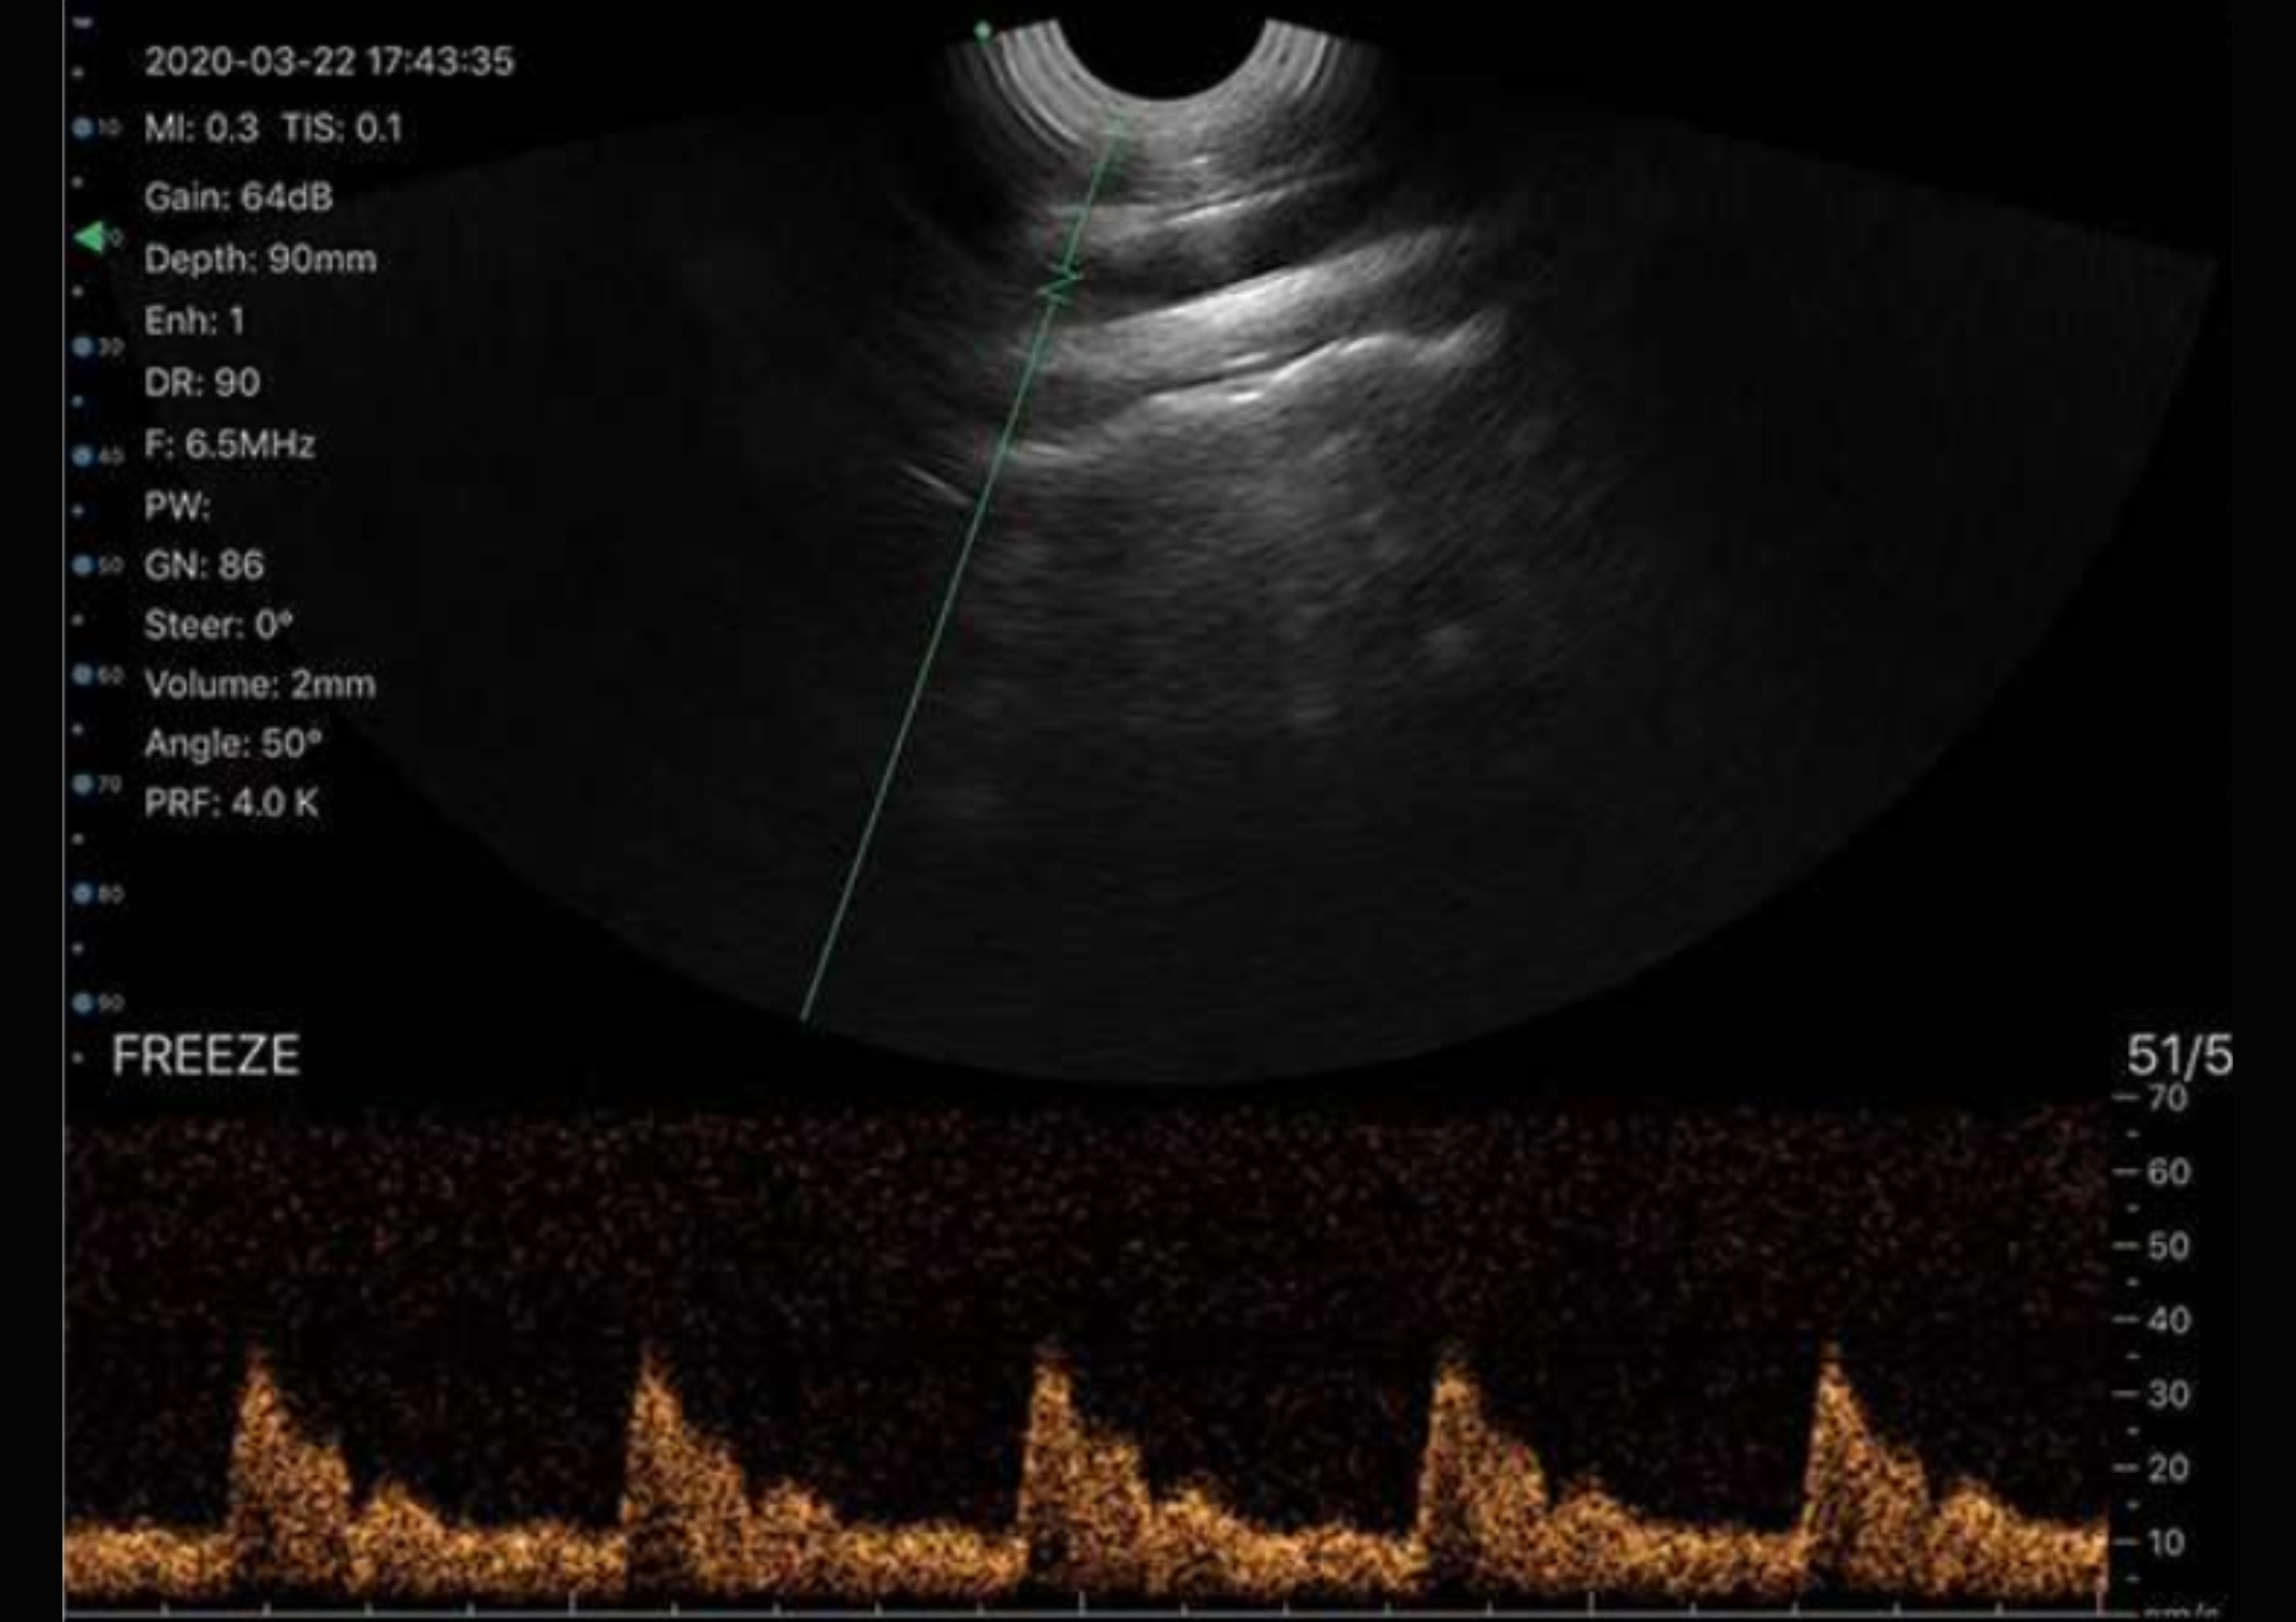

A sonda transretal biplanar oferece a vantagem de visualização em dois planos – transversal e sagital – sem a necessidade de reposicionar o transdutor, o que permite uma avaliação mais completa da próstata e estruturas adjacentes. Essa biplanaridade proporciona maior precisão diagnóstica, facilitando a detecção de lesões prostáticas e a avaliação do volume e simetria da glândula. Além disso, é ideal para procedimentos guiados por imagem, como biópsias, pois permite melhor orientação da agulha, aumentando a segurança. A visualização detalhada também contribui para uma melhor avaliação anatômica das vesículas seminais, uretra prostática e outras estruturas importantes.

Graças à tecnologia biplanar exclusiva, que combina um transdutor micro-convexo e linear na parte endocavitária, o modelo ME Biplanar oferece versatilidade e precisão para exames pélvicos e urológicos com detalhamento excepcional.